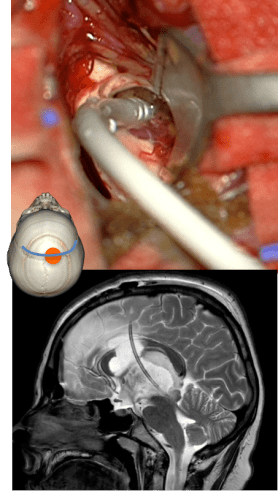

la voie inter-thalamo-trigonale

2 variantes :

- voie sous-choroïdienne : en soulevant la toile choroïdienne

- voie trans-choroïdienne : en décollant le trigone de la toile choroïdienne, ou même en réséquant ce dernier

elle donne accès à la partie moyenne et postérieure du V3, à la région de l’aqueduc, à la

partie haute du mésencéphale,et aux tumeurs naissant à la face interne ou postéro-supérieure du thalamus.

elle est limitée en arrière par la lyre du trigone

elle permet d’aborder des tumeurs de la pinéale à développement antérieur

l’accès à la partie postérieure du V3 nécessite un abord transcalleux un plus antérieur, de façon à être ensuite parallèle au corps du corps calleux (Cf. ci-contre).